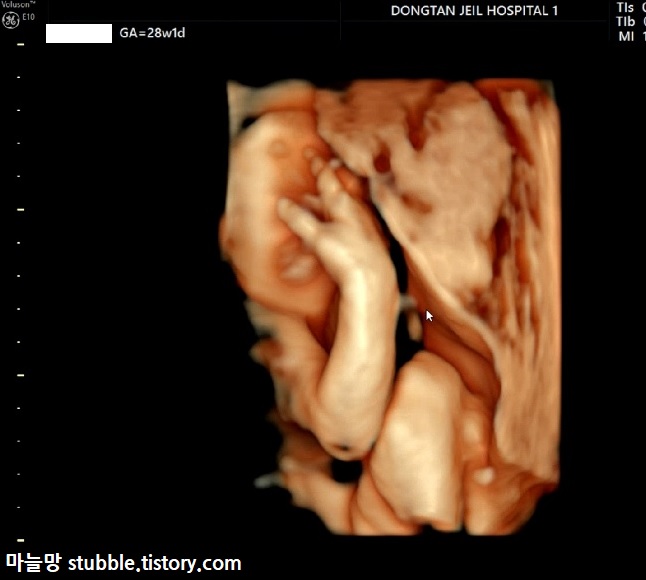

생각보다 아기가 잘 움직인다는 이야기를 듣긴 하였지만 탯줄이 얼굴 위로 지나가고 있었고 아기는 태아 기본자세[?]인 팔을 귀 옆에 두고 절대 내리지 않아서 아주 힘든 초음파를 보게 되었습니다.

그 와중에 얼굴을 가로질러 탯줄이 지나가고 있었는데, 탯줄을 한쪽손으로 잡고 있는 태아의 모습입니다. 탯줄 혈류체크한 것도 보입니다. 입체초음파로 변환했는데도 탯줄은 꽉 잡고 놓지 않았어요.